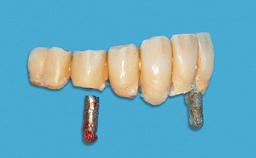

Surgical treatment of a 67-year-old male patient exhibiting an extended edentulous space in the anterior maxilla after the removal of three hopeless incisor teeth.

The video demonstrates implant placement using a surgical stent according to the principle of prosthodontically driven implant placement. The deficient ridge is augmented with locally harvested autologous bone chips, a superficial layer of xenogenic DBBM particles and a resorbable collagen membrane. The surgery is completed with a precise, tension-free primary wound closure.

The case concludes with the presentation of the final prosthesis and the esthetic outcome, demonstrating stable soft tissue conditions and stable bone crest levels at the 3-year follow-up.

# of Implants 2

Type of Implants One-Piece

Prosthesis Type FDP